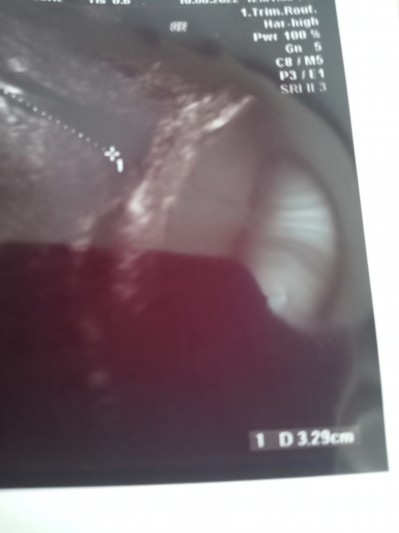

Bu grafik açılmayı mı ifade ediyor?

37+1im kontrole gittim bugün.29 agustusa sezeryan

gün verdi. 3cm yazan açılma mi oluyor?

Hayir rahim agzi uzunlugunu ifade ediyor.

Ultrasonda açılma çıkmaz ki.